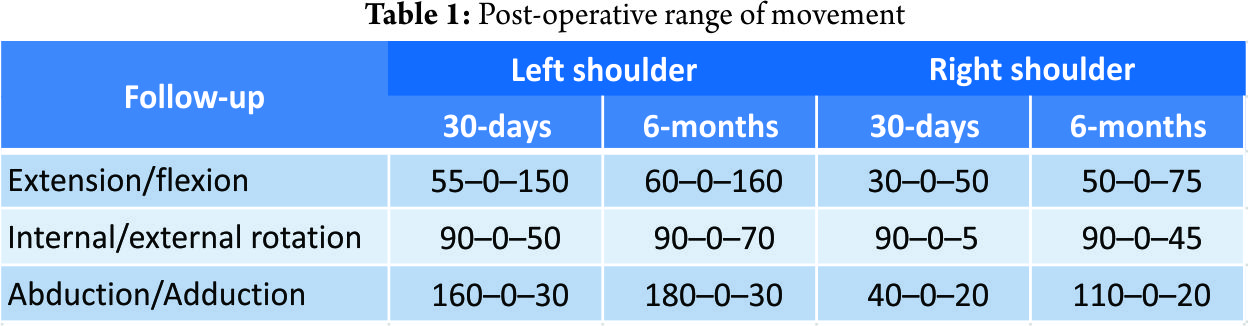

As the patients recovering progressed, a magnetic resonance imaging (MRI) scan of the right shoulder was performed 3-day post-injury to clarify the soft-tissue damage and subsequently a single-row rotator cuff repair using two 5.5 mm TwinFix® anchors (Smith & Nephew; London, United Kingdom) was performed. An additional Pulley-lesion was treated with a biceps tenodesis with fixation of the tendon to the intertubercular sulcus using a 5.5 mm Footprint® anchor (Smith & Nephew; London, United Kingdom). The Hill–Sachs lesion was insignificant and did not require any further treatment (Fig. 2c). Post-operatively, the left shoulder was immobilized in a Velpeau-sling for 4 weeks and the right shoulder in an abduction splint for 6 weeks. Passive mobilization of both shoulders was started immediately on the first post-operative day, followed by increasing active and assistive mobilization. On the right shoulder, progressive adduction and a steady build-up of strength were initiated after 6 weeks. On the left shoulder, full mobilization was allowed following clinical and radiological confirmation of fracture consolidation. Physiotherapy (3 times a week), aquatic therapy (2 times a week), and a 3-week stay in a rehabilitation facility 2-month post-injury completed the post-operative care. The patient was discharged in good general condition with a total inpatient stay of 11 days. The 30-day follow-up assessment showed a still restricted range of movement while the 6-month follow-up assessment demonstrated bilateral considerably improved range of movement (Table 1). At the 2-year follow-up assessment still no evidence of implant failure, recurrence of dislocation or instability was observed.

Outcome

Eleven reviewed cases (31%) report a full recovery bilaterally, whereas twelve cases (34%) report a restricted range of movement bilaterally. Three cases (9%) report both: A restriction in one shoulder and a full recovery in the other. Five reports (14%) remain vague on the patient’s outcome as statements like “reasonable resumption of painless arm movement” or “adequate recovery” let suspect a neither quantified nor published restricted range of movement. No follow-up results were published in four case reports (11%). Out of the fifteen cases with post-reductive restricted range of movement only two cases (13%) have used ultrasound or an MRI scan to assess the rotator cuff. In the remaining 13 reports (87%), the further diagnostic was not considered necessary. Hawkins et al. strengthen the influence of previously undetected rotator cuff tears in patients with an unsatisfying outcome. They have re-evaluated 14 patients with persistent “pain, weakness and functional problems despite an aggressive physiotherapy program” following a shoulder dislocation and discovered in all cases a previously unknown rotator cuff tear [5]. Sonnabend et al. further support this finding in a re-assessment of 13 patients aged 40 years or older who “continued to experience pain and varying degrees of associated weakness” after a primary anterior shoulder dislocation. The authors found “evidence of full-thickness cuff disruption” in all 13 patients – surgical repair was performed in five patients who became subsequently “virtually pain-free” [6]. This emphasizes the need for additional diagnostic imaging such as ultrasound or MRI scans.

Bilateral anterior shoulder dislocations in patients aged 40 years or older are frequently accompanied by proximal humeral head fractures or soft-tissue injuries, especially rotator cuff tears. While the first-mentioned fractures are detectable on the pre- or post-reductive X-ray, the latter-mentioned soft-tissue pathologies are often overseen as required clinical test and imaging are not performed. However, these concomitant injuries – especially the rotator cuff tears – have a significant influence on the outcome [5, 6, 18, 19, 24, 25]. We have shown that soft-tissue imaging was only performed in a total of five of all 35 reviewed cases (14%) and only in two of 15 (13%) cases where a bilateral or unilateral restricted range of movement was present. Even in cases with a significant post-reductive restricted range of movement in rotation and abduction was present, no further diagnostics were conducted and the patient’s poor outcome accepted. Furthermore, we have shown that the previously reported high rate of late diagnosis in bilateral shoulder dislocations is even higher in elder patients suffering from this lesion (15%). Our reported case of bilateral anterior shoulder dislocation assembles a variety of possible concomitant pathologies. Through careful and comprehensive diagnostics all accompanying lesions were detected and subsequently addressed within 5-day post-injury. The patient’s outcome shows that even in older patients with a combination of various bony, cartilaginous, muscular and ligamentous pathologies, good-to-excellent post-reductive and post-operative results are possible if diagnostics are comprehensive and treatment is prompt. In addition, we report the first bilateral shoulder dislocation in winter sports, despite winter sports accounting for a majority of unilateral shoulder dislocations.